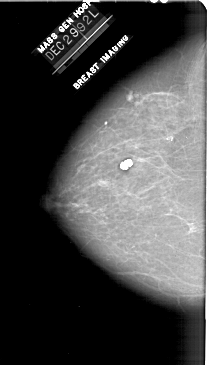

A_1910_1.RIGHT_MLO

RIGHT_MLO LINES 5596 PIXELS_PER_LINE 3226 BITS_PER_PIXEL 12 RESOLUTION 43.5 OVERLAY